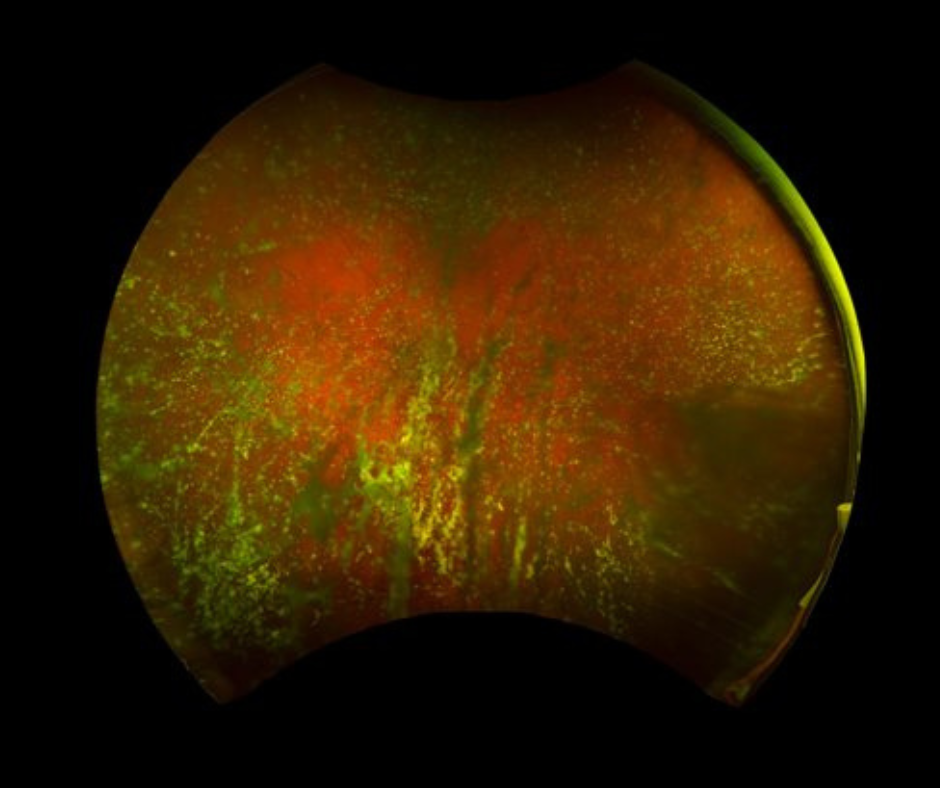

Keeping your children’s eyes safe is a huge part in maintaining healthy vision. Knowing what pediatric retinal diseases are and how to detect early signs are important factors in preventing vision loss. The most common problems with children’s eyes may not be retina related, so examination by your regular eye care professional is key for diagnosis.